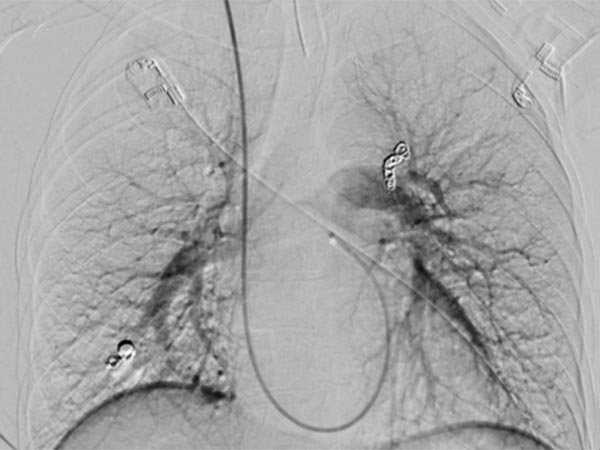

Upon evaluation of the underlying disease, contrast ultrasonography revealed a pulmonary right-to-left shunt, and computed tomography confirmed the finding of multiple pulmonary AVMs. Because of the size, there was an indication for embolization. Digital subtraction angiography demonstrates a pulmonary AVM in the upper lobe, already superselectively catheterized, with typical aneurysmally dilated arteriovenous shunt.

Occlusion of the pulmonary AVM of the upper lobe by insertion of multiple platinum wire loops (coils) via a microcatheter while sparing non-pathological pulmonary arteries.